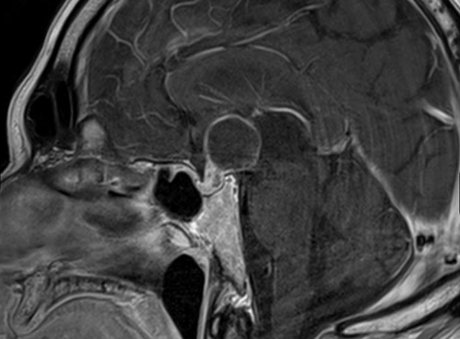

Die Hypophyse (Hirnanhangsdrüse) ist eine kleine, aber entscheidende Hormondrüse im Gehirn. Sie steuert das endokrine System und reguliert über ihre Hormone unter anderem Schilddrüse, Nebennieren sowie Eierstöcke und Hoden. Teilweise wirkt sie auch direkt auf Zielorgane.

Anatomisch liegt die Hypophyse in der Sella turcica (Türkensattel) an der Schädelbasis, direkt unterhalb der Sehnervenkreuzung. Erkrankungen der Hypophyse können daher neben hormonellen Störungen auch Sehstörungenverursachen. Die Drüse besteht aus Vorderlappen (Adenohypophyse), Pars intermedia und Hinterlappen (Neurohypophyse).

Das Hypophysenadenom, heute zunehmend auch als pituitäres neuroendokrines Tumorleiden (pitNET) bezeichnet, ist eine meist gutartige Neubildung aus Zellen des Hypophysenvorderlappens. Durch das Tumorwachstum kann gesundes Hypophysengewebe in der knöchernen Sella turcica verdrängt werden, was zu einem Hormonmangel (Hypopituitarismus) führt. Dabei können einzelne Hormone oder mehrere Hormonachsen betroffen sein. Wächst der Tumor nach oben, kann er auf die Sehnervenkreuzung drücken und Sehstörungen verursachen.

Raumforderungen der Schädelbasis, insbesondere Hypophysenadenome, können – abhängig von ihrer Größe – von unten auf die Sehnervenkreuzung (Chiasma opticum) drücken und dadurch Sehstörungen verursachen. Typisch ist die Entwicklung eines Gesichtsfelddefekts, bei dem sich der wahrnehmbare Sehbereich schleichend verkleinert.